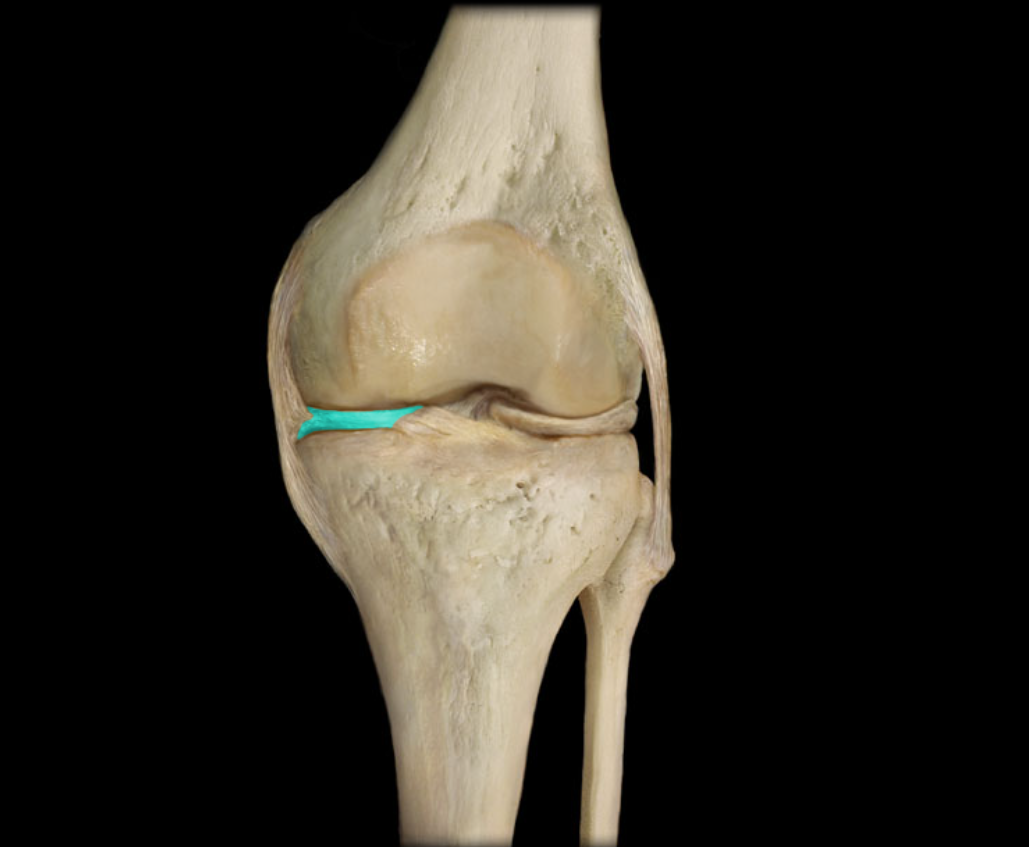

Medial meniscus

Lateral meniscus